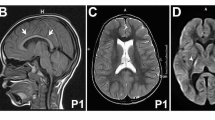

a On the left: T1-weighted sagittal brain MRI of individual 1A at age 4 years, showing mild atrophy of the anterior superior cerebellar vermis. On the right: T2-weighted MRI brain showing early bilateral frontal atrophy at age 2 years. Full MRI sequence analysis revealed no sulcation abnormality for individual 5. b Schematic representation of P4-ATPase ATP8A2 protein with ten transmembrane helixes (1–10), A (actuator), P (phosphorylation), N (nucleotide binding) domains, adapted from Vestergaard et al. [18], and showing localizations of the mutations previously reported (italics) and described in this study (bold and underlined). Compound heterozygous mutations are indicated by dotted boxes. Compound heterozygous A544P and R625W were found in a patient described by Martin-Hernandez [6]. c Amino-acid sequence comparison of orthologous P4-ATPase ATP8A2. Amino acid changes described in our study (bold and underlined) are predicted to be pathogenic (isoleucine 215, methionine 438, glycine 585 and arginine 588 are highly conserved up to invertebrates and fungi)

Two siblings (individual 1-A and 1-B) born from first-degree consanguineous parents of Turkish origin were affected by 2 years of age with head titubation, ataxic gait and tremor. Both siblings have borderline intellectual functioning with IQ ranging from 70 to 80. Cerebral magnetic resonance imaging (MRI) revealed very mild vermian atrophy in the brother at 4 years (Fig. 1a). Both patients were still ambulant, with unilateral aid, by ages ranging from 8 to 11 years.

Individual 4 is a 28 year old female with Italian origin who is wheelchair-bound. She presents with a similar phenotype to that of individual 3 but with severe intellectual disability, anarthria, strabismus and without optic atrophy. EEGs were normal up to the age of 17 years, and then revealed focal paroxysms and slow wave activity. MRI at the age of 5 years and 11 years showed microcephaly, oligogyria with few shallow sulci, bilateral moderate thinning of white matter, mild thinning of the corpus callosum and normal cerebellum.

Individual 5 is a 2 year old boy from Turkey who presents with developmental delay, intellectual disability, severe hypotonia, muscle weakness, chorea, dystonia, facial dyskinesia, strabismus, severe ptosis, ophthalmoplegia, hearing impairment and bilateral frontal atrophy on brain MRI. At 24 months, he experienced generalized febrile seizures. Two routine EEGs obtained at different timepoints showed no epileptiform abnormality. He also has feeding difficulties.